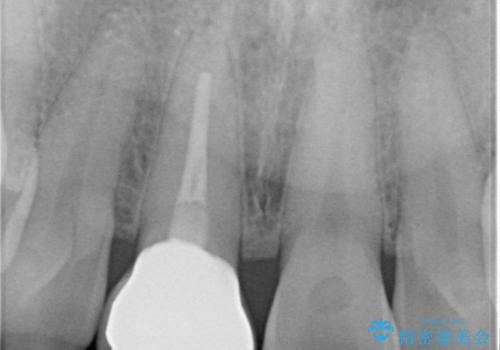

- 数年前に前歯のセラミック治療を行い、そのやり替えを希望して来院された患者様です。

先端が欠けてしまっていて、色も少し不自然な印象があります。

空隙がある歯並び改善のため、矯正治療も提案しましたが希望せれず、隣の歯も一緒に被せものにして、

大きさをそろえることも希望されなかったため、一本だけやり替えていくととしました。